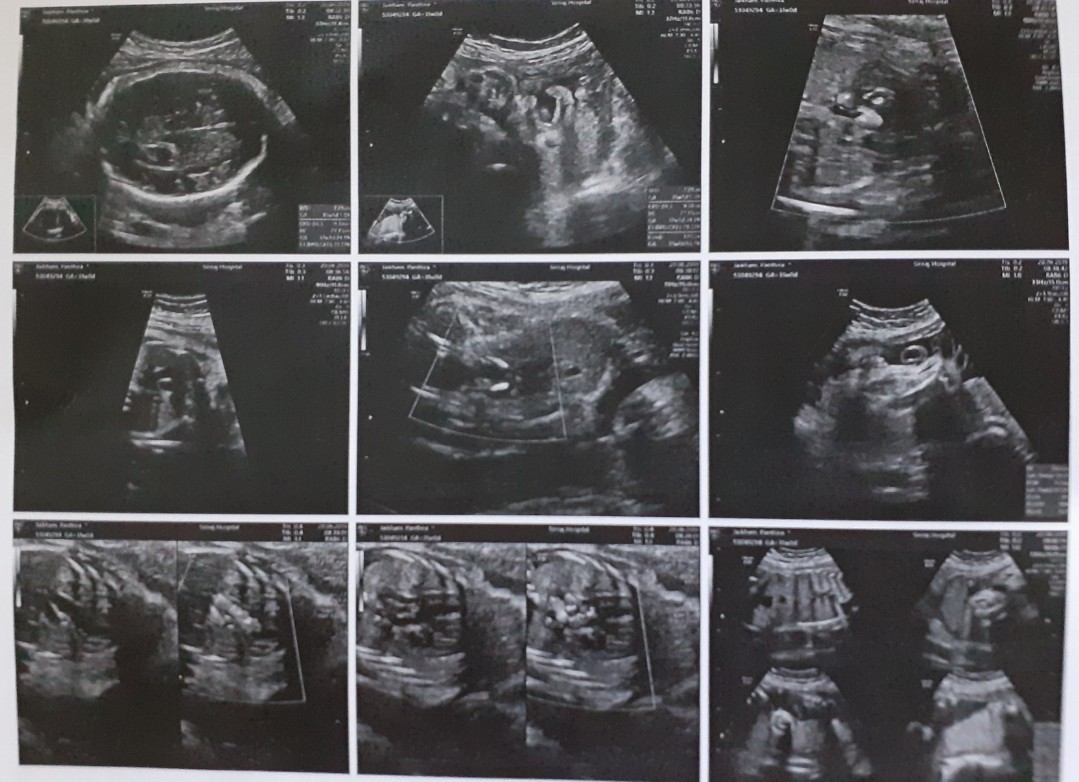

ล่าสุด 31week

เรามีตอน 14 w ค่ะ

ตอน16w 4dค่ะ☺️👶